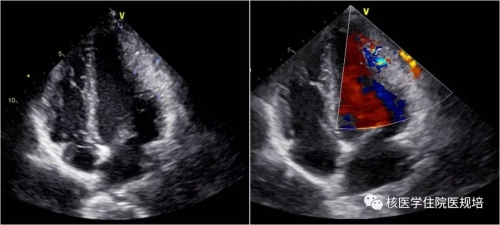

患者男性,20岁,2月前因发热待查就诊,影像学检查发现心脏占位。心脏超声示:左室前侧壁占位,彩色多普勒血流成像可见肿物血供丰富(图1);心脏MR示:左室中段及心尖段前侧壁占位,累及前组乳头肌,前侧壁可见粗大肿瘤血管(图2)。为明确左心室病变性质,行18F-FDG PET/CT显像(图3)。

图1